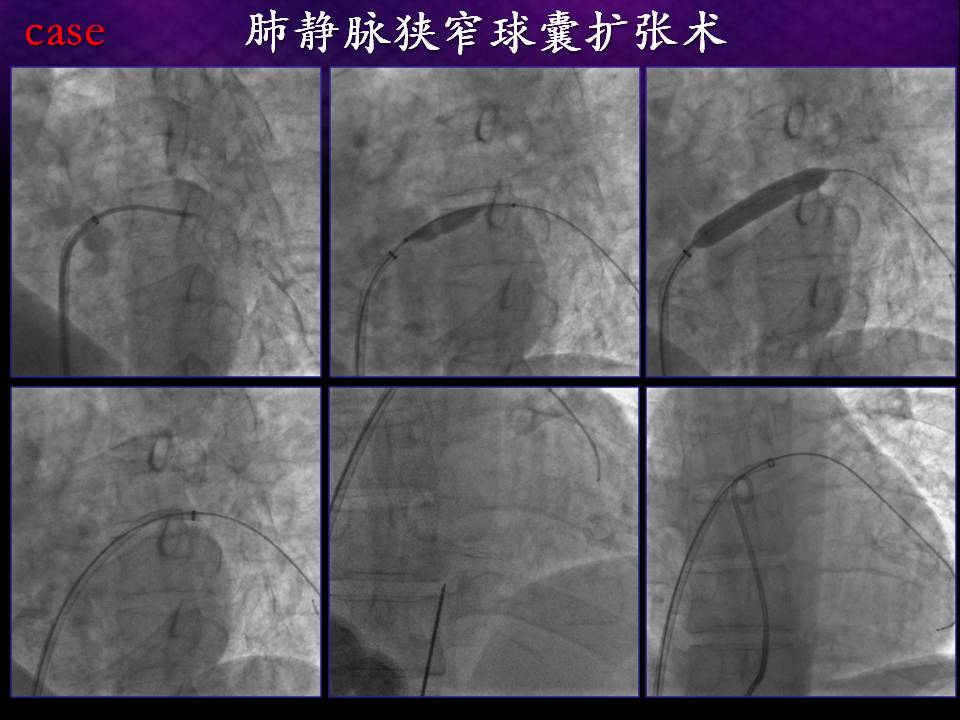

三维时代肺静脉狭窄的预防与处理